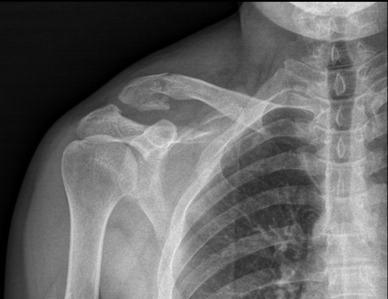

Patient D., a 39-year-old male of Kazakh origin, presented with right shoulder pain and impaired upper limb function following a fall onto the right shoulder approximately two hours prior to admission. The symptoms developed immediately after the injury. The right upper limb was initially immobilized using a sling bandage. Upon removal, swelling and deformity of the right shoulder were observed. Palpation revealed marked tenderness, crepitus, and abnormal mobility at the acromial end of the clavicle. Shoulder motion was restricted due to pain, but there were no signs of sensory deficits or numbness in the affected limb. A physical examination was performed, followed by radiographic evaluation.

X-ray imaging demonstrated a displaced comminuted fracture of the distal clavicle (Figure 2), with the proximal fragment displaced superiorly. The fracture was classified as type IIb according to Neer.